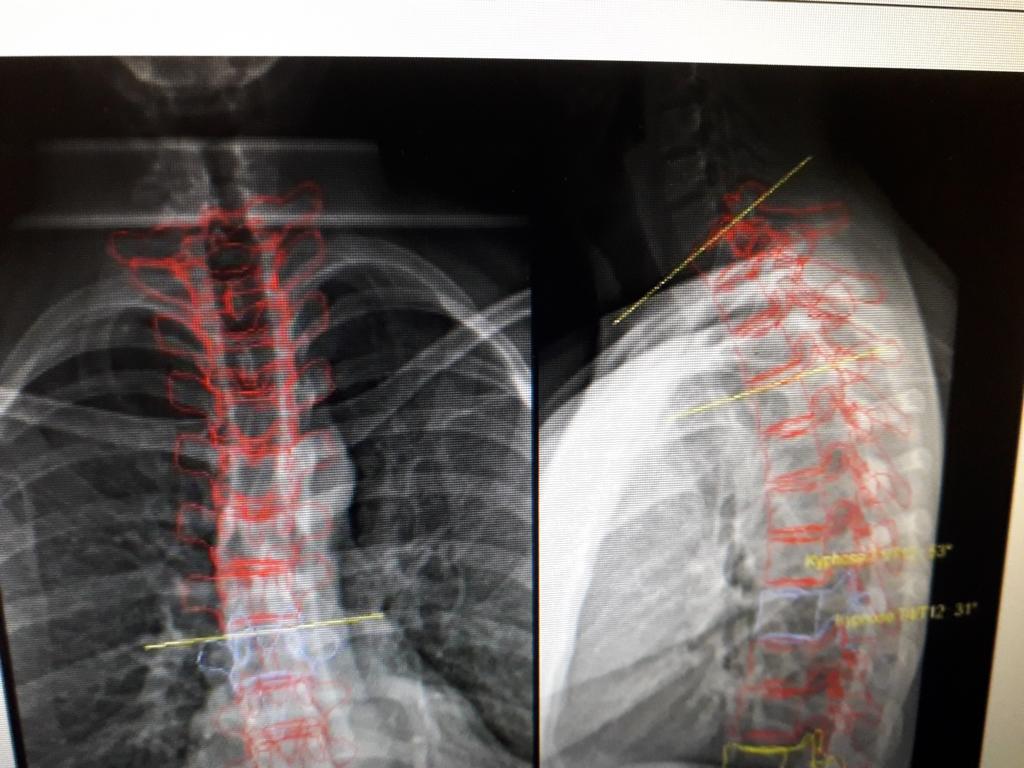

Aber anhand des Teilwirbelsäulenbildes 1 wird jetzt klar, dass die Kyphose deutlich höher liegt, als normal. Als Vergleich habe ich eine entsprechende Grafik angefügt. Diese könntest Du neben Deine "gebastelte" verbesserte Gesamtaufnahme legen und Dir auch vorstellen, welche Korrektur bzw. Korrekturbewegung erforderlich ist. Möglicherweise ist das der Grund, warum die Therapeuten diese Kombination gegen Flachrücken/Rundrücken gewählt haben. Man muss direkt sehen und auch fühlen, was da durch was wie passiert. ;)

Dateianhänge

Wirbelsäule.jpg

Wirbelsäule.jpg (12.52 KiB) 31898 mal betrachtet